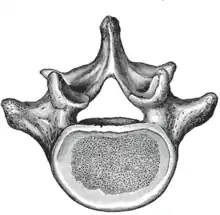

يصف الشكل المقابل الخصائص العامة للفقرات القطنية من الأولى إلى الرابعة. تمتلك الفقرة الخامسة خواص معينة، وهي مفصلة أدناه. كما هو الحال مع الفقرات الأخرى، تتكون كل فقرة قطنية من جسم فقري وقوس فقري. القوس الفقري المكون من زوج من العنيقات وزوج من الصفائح، يحيط بالثقب الفقري (فتحة) ويدعم سبع نتوءات.

الجسم

الجسم الفقري لكل الفقرات القطنية كبير، وهو أوسع من جانب إلى آخر أكثر منه من الأمام إلى الخلف، وأسمك قليلاً في الأمام منه في الخلف. وهو مسطح أو مقعر قليلا أعلى وأسفل، ومقعر من الخلف، وضيق بشدة في الأمام وعلى الجانبين.[5]

القوس

العنيقات تكون قوية جدا، ومتجهة إلى الوراء من الجزء العلوي في الجسم الفقري. وبالتالي فإن الشقوق الفقرية السفلية يكون لها عمق كبير.[5] تختلف العنيقات في الشكل من القطنية العلوية إلى القطنية السفلية. وهي تزداد في العرض السهمي من 9 ملم إلى 18 ملم في القطنية الخامسة. وتزداد في التزوية في المستوى المحوري من 10إلى 20 درجة بحلول الفقرة القطنية الخامسة. تستخدم العنيقة أحيانًا كبداية المدخل إلى الجسم الفقري للتثبيت بمسامير عنيقية أو لوضع إسمنت عظمي كما هو الحال في تقويم رأب الفقرة أو رأب العمود الفقري.

الصفائح تكون عريضة وقصيرة وقوية. [5] إنها تشكل الجزء الخلفي من القوس الفقري. في المنطقة القطنية العلوية تكون الصفيحة أطول من كونها عريضة ولكن في الجزء القطني السفلي تكون الصفيحة أعرض من كونها طويلة. تربط الصفيحة بين النتوء الشوكي والعنيقات. الثقب الفقري داخل القوس يكون مثلث، وأكبر منه في الفقرات الصدرية، ولكنه أصغر منه في الفقرات العنقية.[5]

النتوءات

النتوء الشوكي سميك، وواسع، ورباعي الأضلاع إلى حد ما؛ إنه يتجه إلى الوراء وينتهي بحدود خشنة غير متكافئة، وأسمك من الأسفل حيث يكون مشقوق في بعض الأحيان.[5]

النتوءات المفصلية العلوية والسفلية محددة جيدًا، حيث تتجه على التوالي لأعلى ولأسفل من مفارق العنيقات والصفائح. وجوه النتوءات العلوية تكون مقعرة، وناظرة إلى الوراء وإنسية، بينما تلك الموجودة على المستوى السفلي تكون محدبة، ومتجهة إلى الأمام ووحشية. الأولى تكون أعرض باستثناء الثانية حيث أنها في العمود المفصلي، النتوءات المفصلية السفلية تكون محاطة بواسطة النتوءات العلوية للفقرة أسفل منها.[5]

النتوءات العرضية طويلة ونحيلة. فهي أفقية في الفقرات القطنية الثلاثة العلوية وتنحدر قليلاً إلى الأعلى في الفقرتين السفليتين. في الفقرات الثلاث العليا تخرج من مفارق العنيقات والصفائح، ولكن في الفقرتين السفليتين فهى تقع إلى الأمام أكثر وتنبع من العنيقات والأجزاء الخلفية من أجسام الفقرات. تقع أمام النتوءات المفصلية بدلاً من خلفها كما هو الحال في الفقرات الصدرية، وهي متجانسة مع الضلوع. [5]